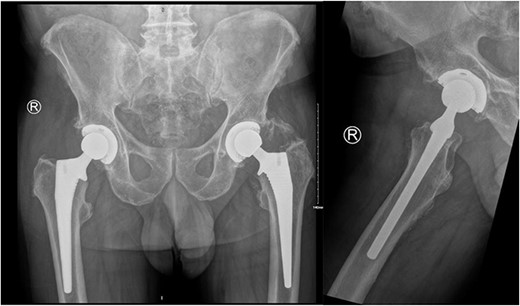

Subsequently, this patient’s case was discussed at our PJI multidisciplinary meeting among the infectious diseases, microbiology, and orthopaedic teams. A consensus decision was made to treat the patient with a 12-week course of IV Vancomycin given the clinical presentation, radiological, and intraoperative findings. After completing his 12 weeks of IV antibiotics, his inflammatory markers returned to normal limits (Fig. 5). At 6-month follow-up, our patient was mobilizing independently without any signs of infection recurrence. His radiographs showed the implant was in a satisfactory position with no evidence of loosening (Fig. 6).

AP pelvis and lateral right hip radiographs at 6 months post debridement, antibiotics, implant retention (DAIR) procedure.